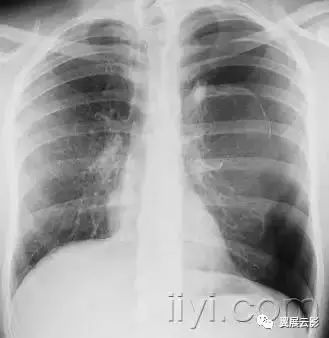

十九、肺实变:

平片和CT:肺实变表现为肺实质密度的均匀一致性增高,导致肺血管和气道壁边缘不清。有时可见含气支气管征。只有在极少数的情况下,肺实变的密度变化有助于鉴别诊断,例如脂性肺炎是密度减低,胺碘酮中毒时密度增高。

图示为多灶性的肺实变。